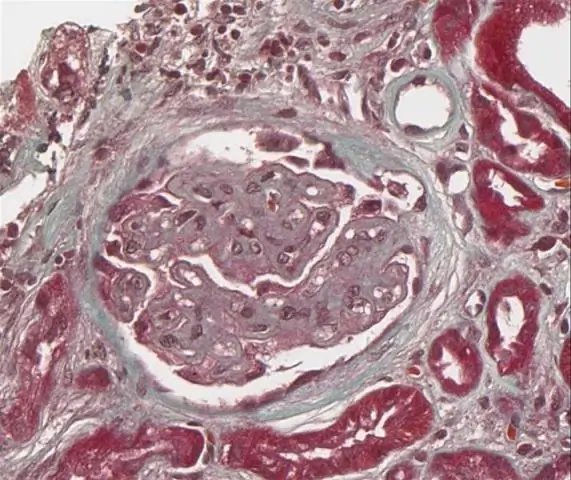

IgA нефропатия (IgAN), также известная как болезнь Бергера (/ b?? r? E? /) (И варианты), или синфарингитный гломерулонефрит, представляет собой заболевание почек (или нефропатия ) и иммунная система; в частности, это форма гломерулонефрита или воспаления клубочков почек.

Гломерулонефрит относится к воспалению клубочка, который является единицей, участвующей в фильтрации в почках. Это воспаление обычно приводит к одному или обоим нефротический или нефритический синдромы.

IgA нефропатия является наиболее частой формой гломерулонефрита. Нефротический синдром встречается в 5-10% случаев IgA нефропатия, (5) хотя в двух исследованиях из Китая сообщается, что у детей частота составляет более 30%. Кроме того, в нескольких исследованиях было показано, что протеинурия является предиктором исхода в Нефропатия IGA.